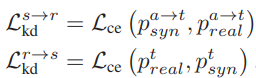

또한 이런 직접적인 학습 뿐만 아니라 반대쪽 segmentation 모델의 예측을 사용해서 간접적인, mutual한 학습을 하게 됩니다. 위 그림에선 L_{kd}가 이에 해당하게 됩니다.

흥미로운 점은 KD loss가 흔히 사용하는 kl divergence loss가 아닌 그냥 cross entropy loss를 사용했다는 점이네요. 사실 mutual 기법에서 kl divergence 를 사용하는 것은 통상적으로 모두 적용하는 것이라 생각했었는데, CE를 사용했네요. 이에 대한 고찰은 없어서 저자의 의도는 알 수 없었습니다.

그리고 위의 직접 학습과 간접 학습을 결합하여 S_{real}과 S_{syn}를 학습시키는 LOSS는 아래 식과 같습니다.